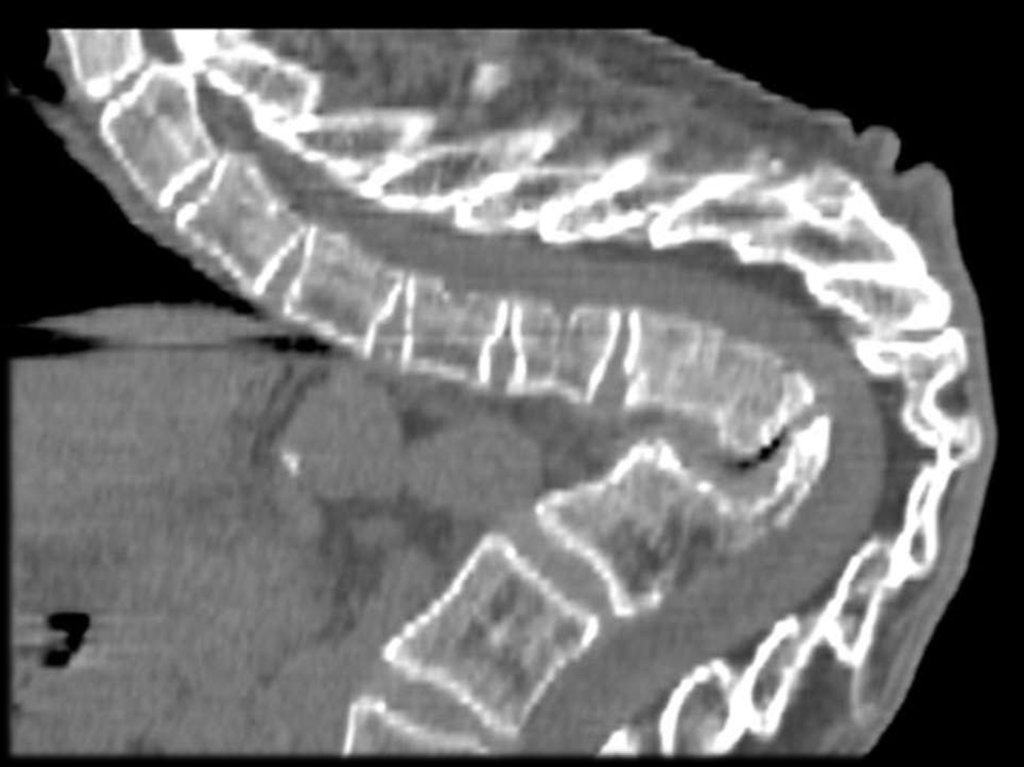

Слева — бруцеллезный спондилит поясничного

отдела позвоночника. Справа — двухсторонний

бруцеллезный сакроилеит.

Поражение позвоночника при хроническом бруцеллёзе